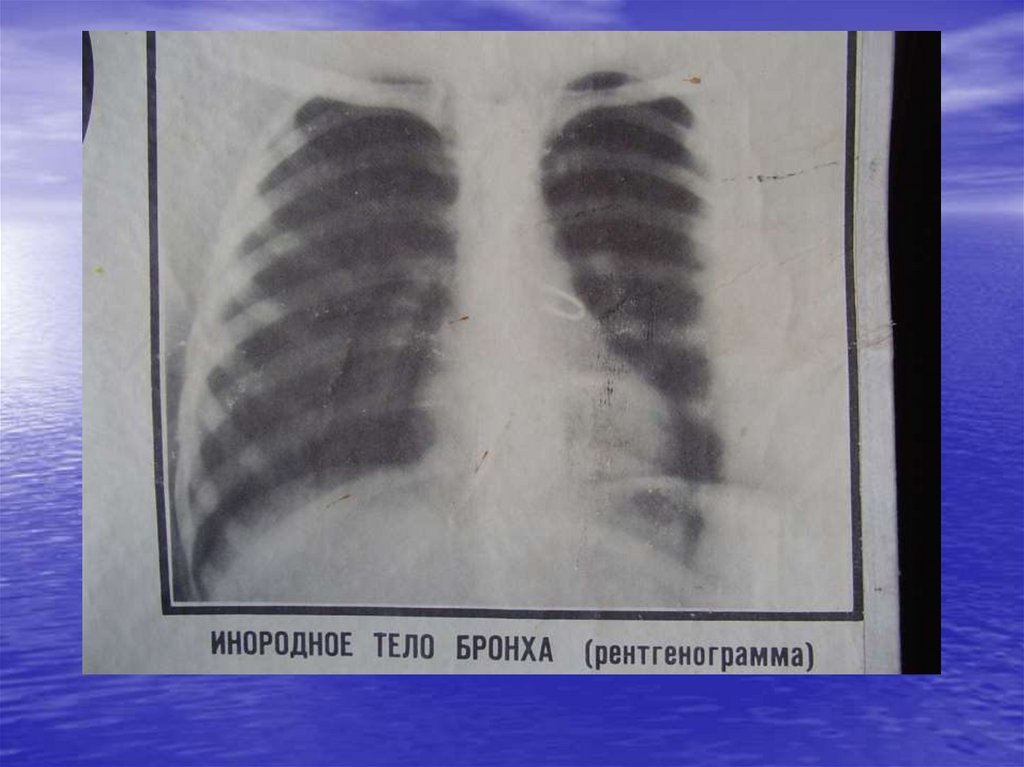

Инородные тела уха